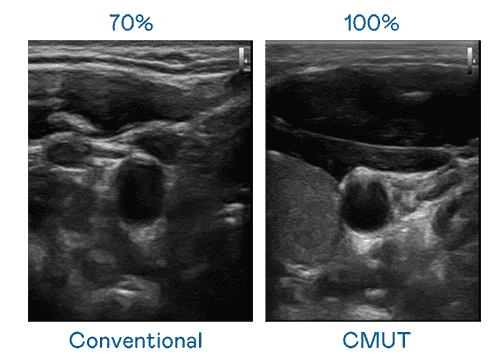

CMUT 技术是一种用电容式微机电元件来产生超音波讯号的技术。。。与传统 PZT 压电式技术相比,,CMUT 频宽增加 30%,,更宽频的超音波讯号让影像解析度大幅提升,,,,是实现高影像品质医疗超音波扫描、、、促进精准医疗发展的关键技术。。。。

大频宽带来超清晰影像

超音波影像的解析度高低,,首先取决于探头能发出的讯号频宽。。。OBPay CMUT 可提供高清晰的超音波讯号,,提供高频宽、、、、高灵敏度、、、影像纹理细节更高的超音波影像,,,,协助医护人员缩短影像判读时间及利用精准的医疗影像进行诊断。。。